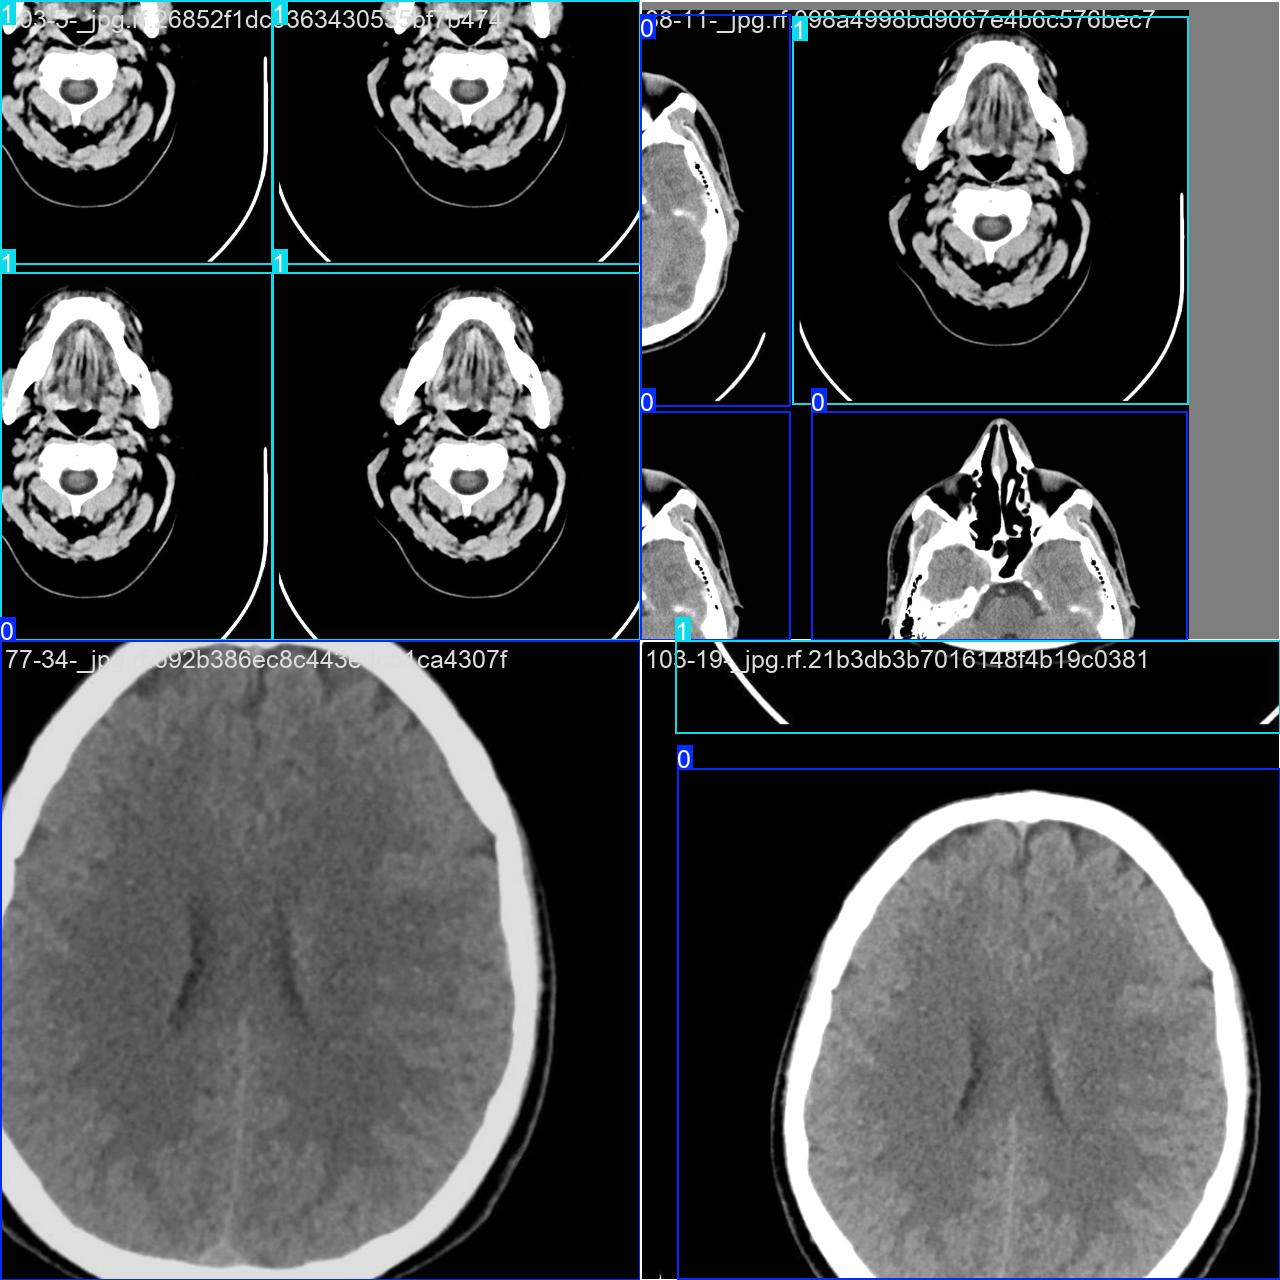

该数据集用于脑中风病症目标检测任务。

类别:2类[‘出血性脑卒中’,’缺血性脑卒中’

标签(names): [‘Hemorrhagic’, ‘Ischemic’]

目标检测训练数据可视化

目标检测训练过程中,模型对数据的可视化结果,主要展示了多个类别目标的检测边框和类别标注情况。整体检测表现较好,但可以通过优化标注和模型训练进一步提升精度和鲁棒性。